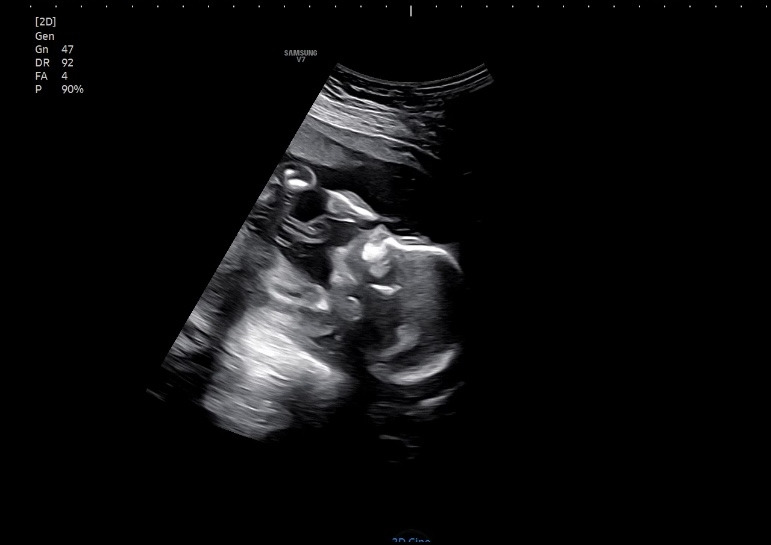

여행 다녀와서 바로 병원에 가봤는데, 건강하게 잘 있었다. 초음파를 보자마자 엄마를 정면으로 보고 있어서 아내는 깜짝 놀랐다고 한다. 우리 딸 여행 재밌었다는 거지???